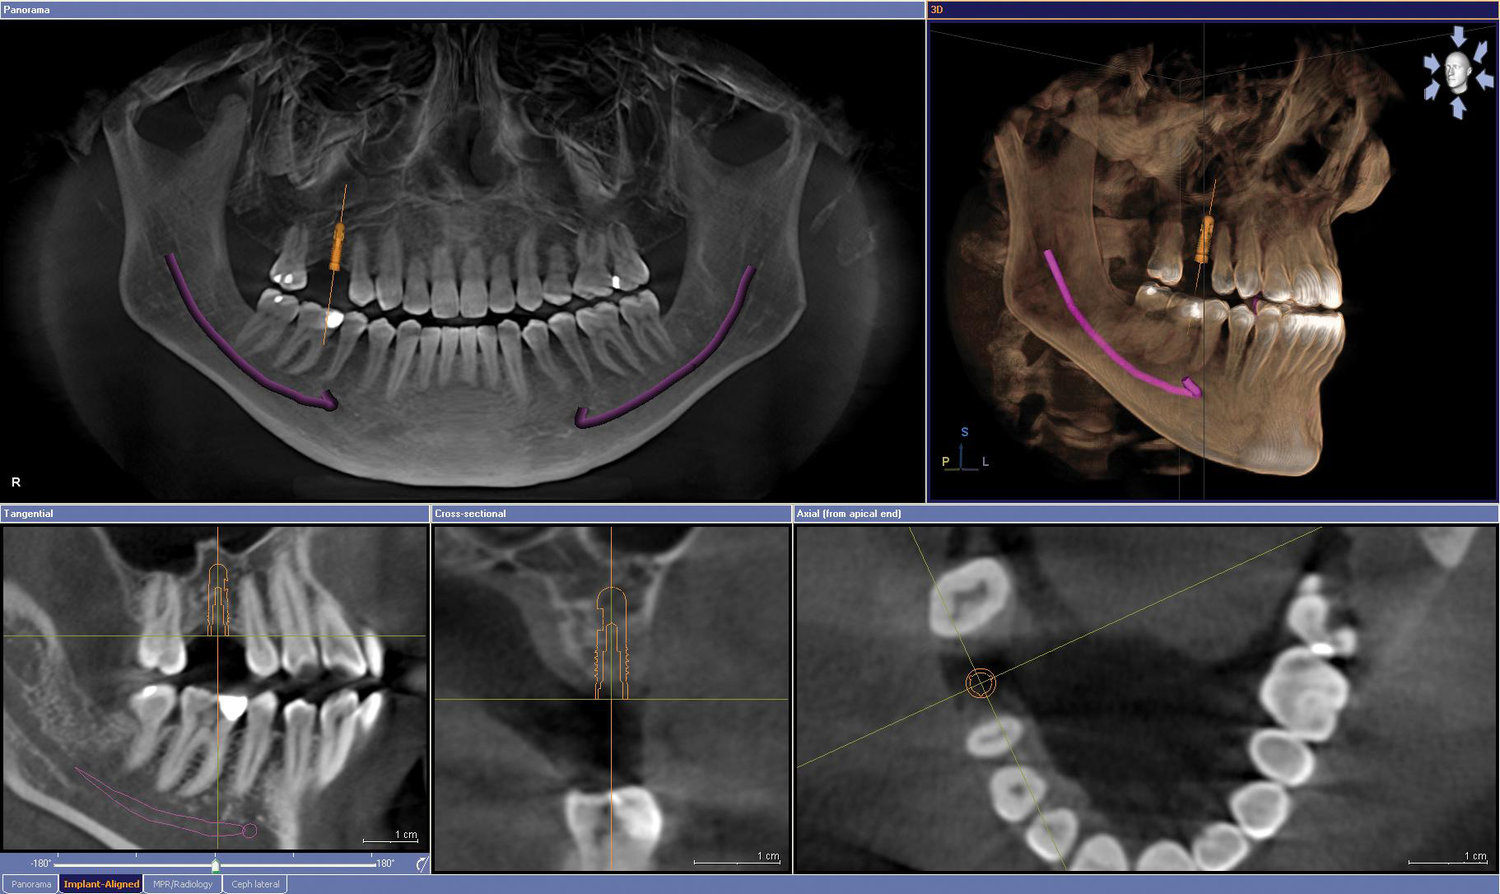

دانستنی های CBCT

CBCT چیست؟CBCT دندانپزشکی از پیشرفت های بسیار مهم در تکنولوژی تصویربرداری دندان می باشد. این روش جدید امکان مشاهده سه ...